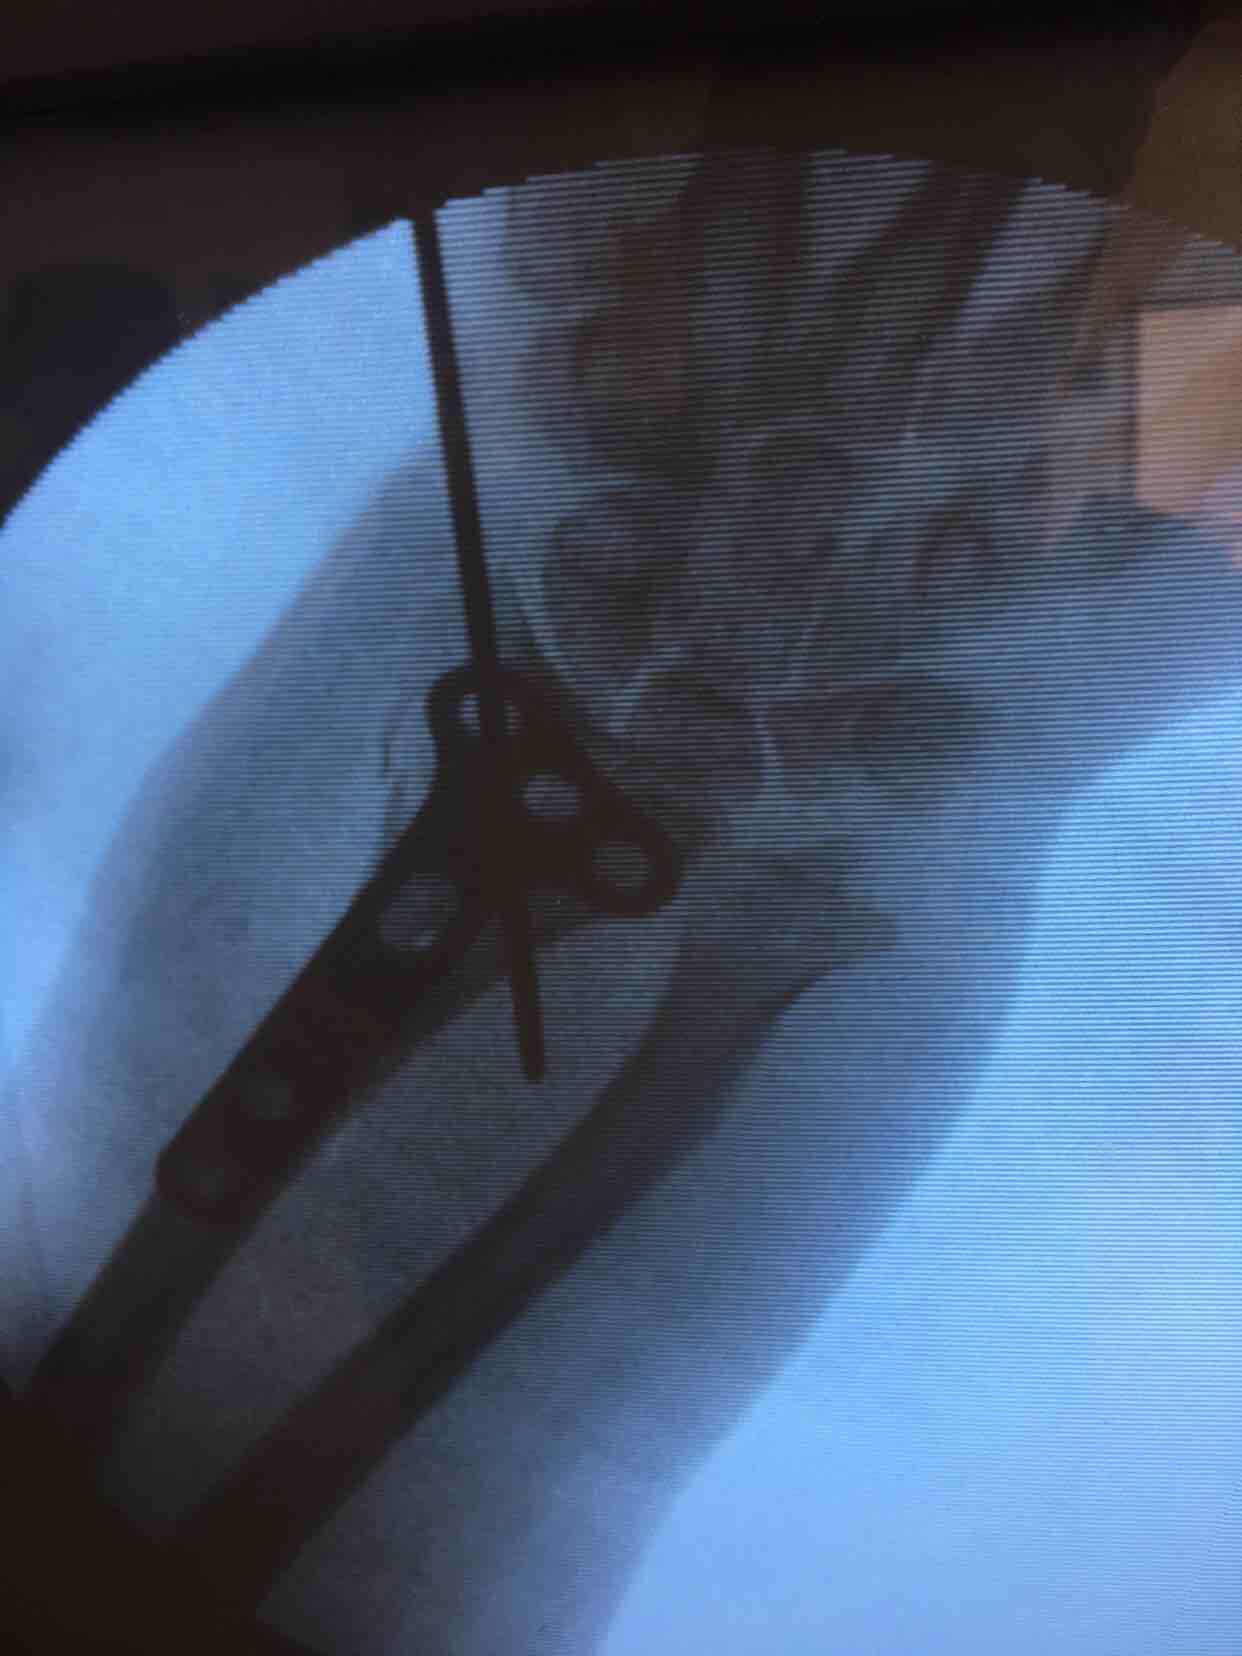

诊断尺桡骨远端粉碎性骨折在臂丛麻醉下行切复内固定术,术中克氏针临时固定,维持复位,术后石膏托固定,抗炎,消肿等处理。